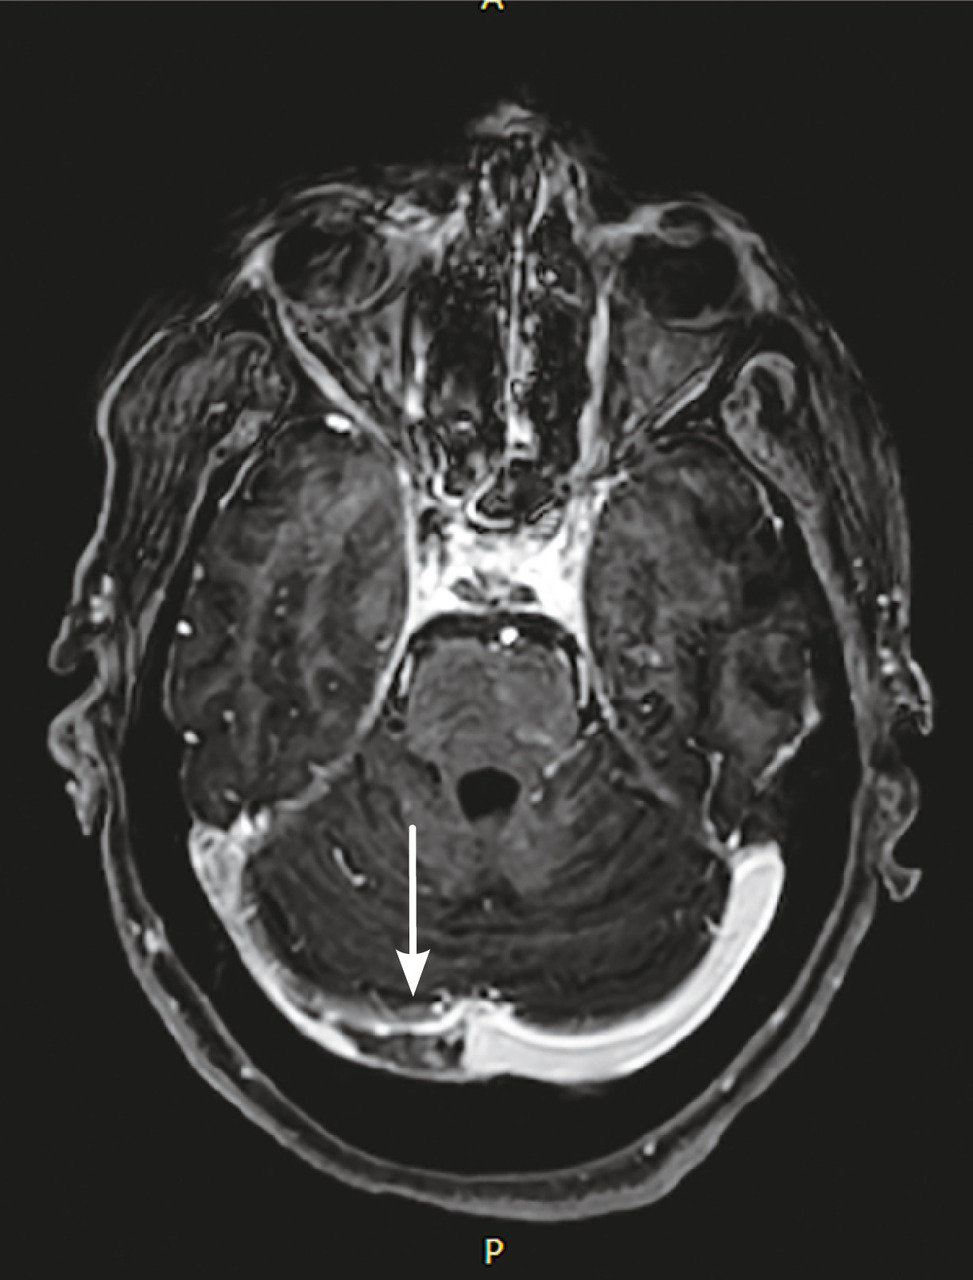

Cette femme de 45 ans était admise aux urgences à la suite d’une hémiplégie gauche. Une imagerie par résonance magnétique (IRM) cérébrale montrait un accident vasculaire cérébral ischémique aigu du territoire de l’artère cérébrale moyenne droite (fig. 1 ) avec occlusion de l’artère carotide droite. Par ailleurs, il y avait un comblant otomastoïdien droit (fig. 2 ) avec collection abcédée parapharyngée homolatérale (fig. 2 ) et thrombose de la veine jugulaire interne droite étendue au sinus sigmoïdien et latéral (fig. 3 ). Après 21 jours d’antibiothérapie intraveineuse combinée à l’anticoagulation, l’IRM de contrôle montrait une recanalisation de la carotide interne et de la veine jugulaire interne.

Le syndrome de Lemierre est une entité rare et potentiellement grave, définie par la survenue d’une thrombophlébite cérébrale touchant la veine jugulaire interne ou ses bran-ches. Il est dû, le plus souvent, à une infection par Fusobacterium necrophorum.1 Le site initial est généralement oropharyngé. En l’absence d’une antibiothérapie précoce et adaptée, ce syndrome peut rapidement évoluer vers une septicémie et à la dissémination par voie hématogène à d’autres sites métastatiques.2 L’occlusion de la carotide interne et la survenue d’un infarctus cérébral sont des complications extrêmement rares et exceptionnelles de ce syndrome.